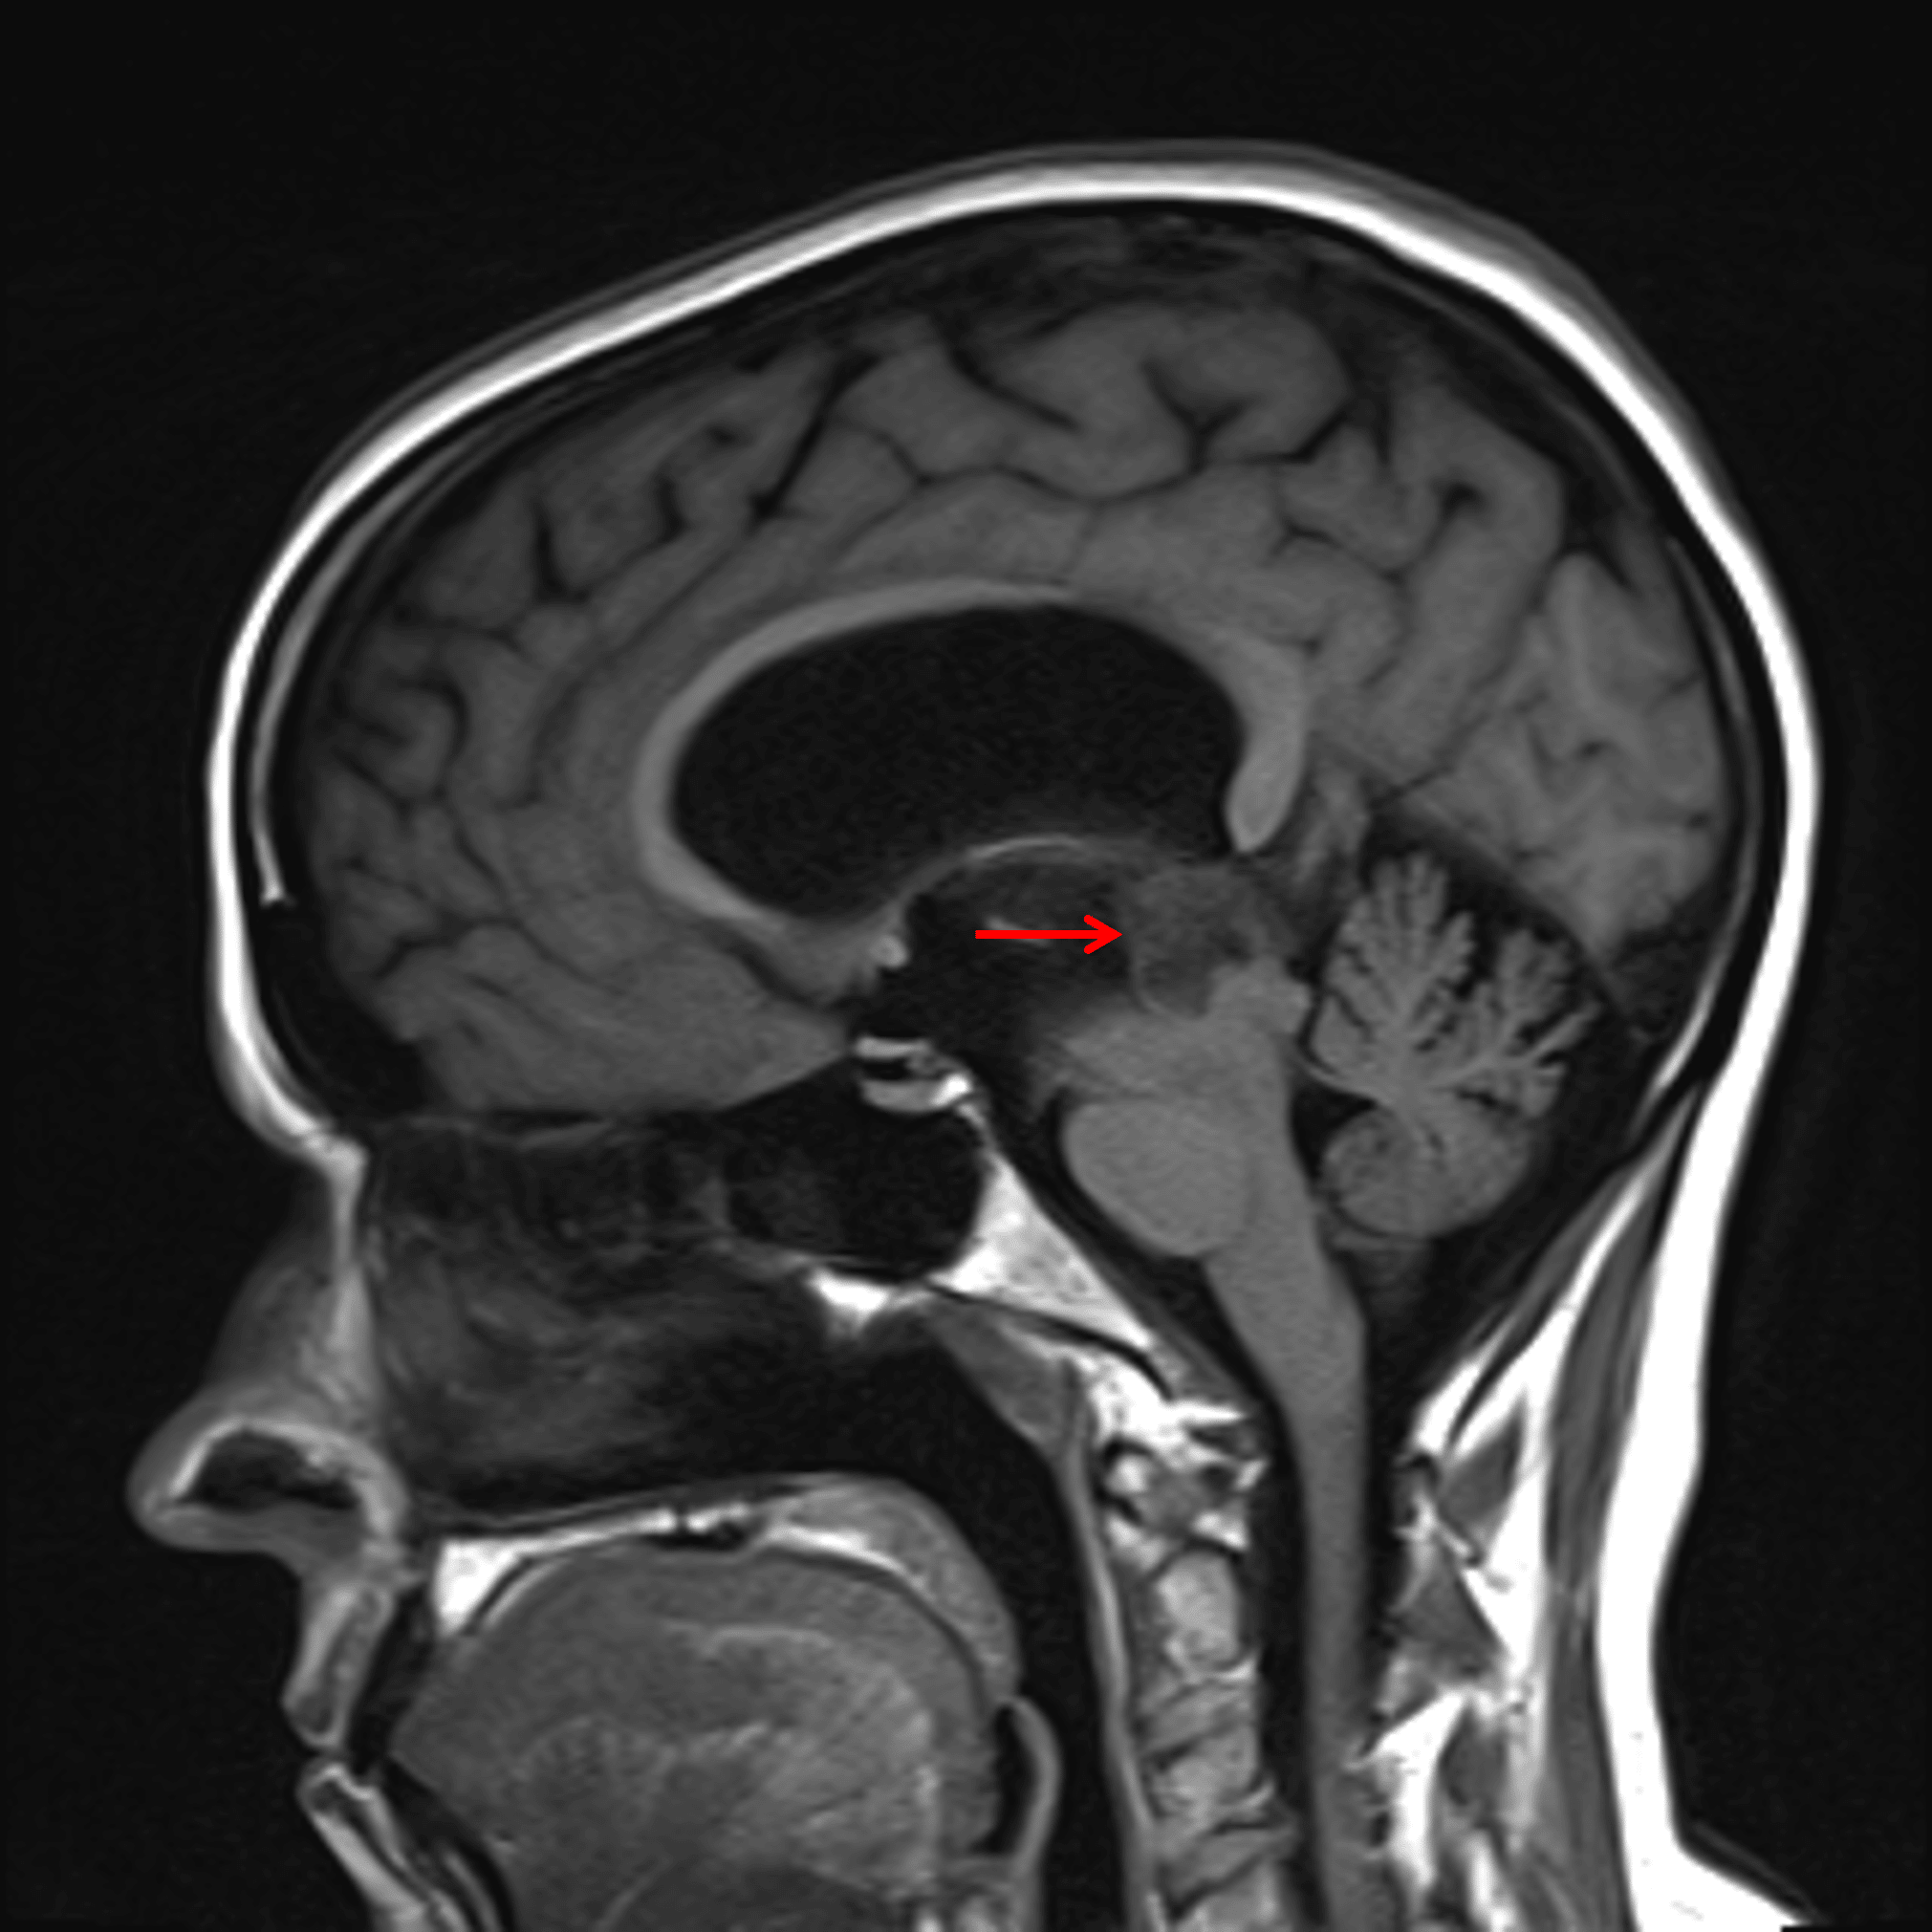

The mass has an internal cystic component with avid enhancement of the solid components (red arrows).